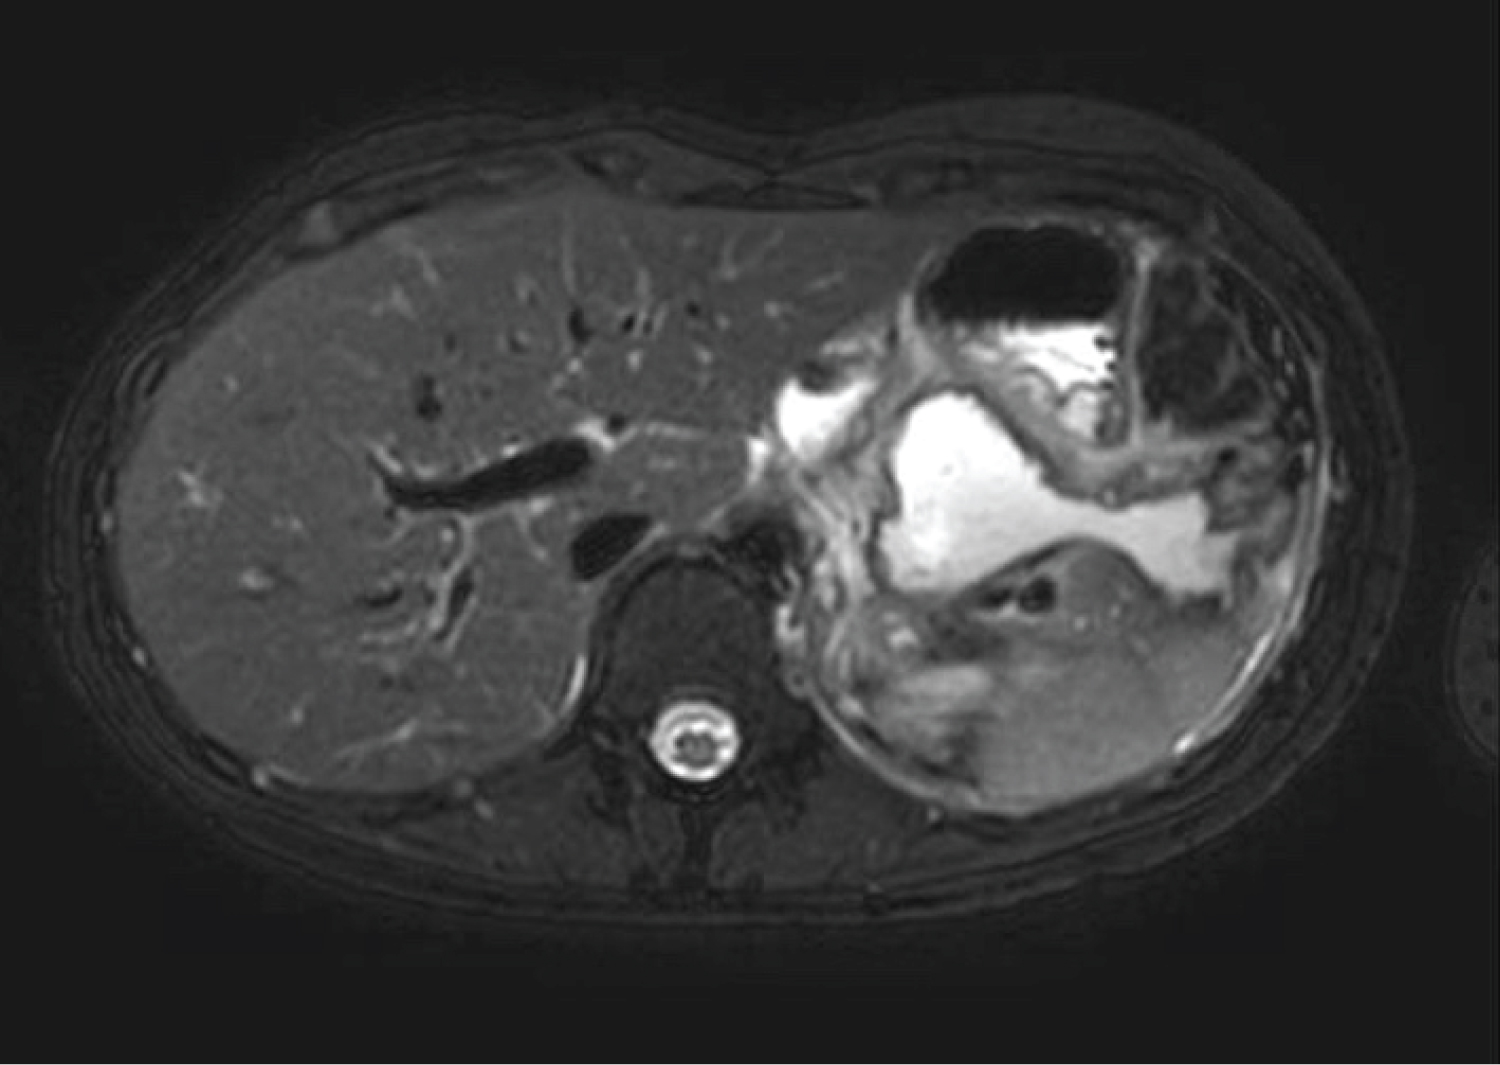

In Figure 2a, a 19-gauge Cook needle (Cook, Bloomington, IN, USA) was then introduced into the lesser sac collection and a large volume of clear pancreatic fluid aspirated. A 0.035 soft Jag wire with subsequent cystotome to puncture across the gastric wall was performed. A second wire was placed into the cystotomy with a 7 French 4 cm double pigtail stent deployed (Figure 2b). Figure 3 demonstrates the cystoenterostomy performed in case 6, with stent position in duodenum. With EUS guidance, the entire procedure was performed under direct vision, thus preventing vascular injury. Post discharge, all patients were reviewed in hepatobiliary surgery outpatient clinic for assessment of symptom resolution.